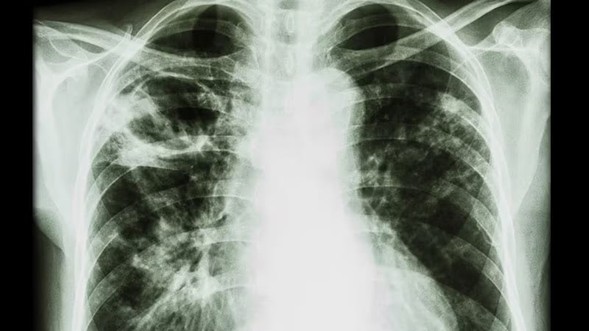

Paciente masculino de 23 años quien es llevado a consulta por productiva, malestar general fatiga y

disnea. Menciona además que últimamente ha tenido que utilizar más veces al día

su tratamiento de rescate para asma. Entre los antecedentes menciona que cree

que la Pachamama es perfecta, así que se come todas las verduras tal cual las

recoge de la siembra sin lavarla ni hervirla. Además, menciona tener malestar

abdominal, dolores tipo cólico, náuseas, meteorismo, vómitos ocasionales y

diarrea. Se le realiza un examen de heces que menciona que tiene

"huevos" y una biopsia pulmonar que verán a continuación... Con base

a toda la información... ¿Cuál de las siguientes radiografías torácicas es más

probable que tenga este paciente?